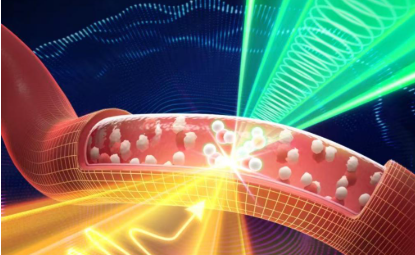

北大新突破:一滴血 查清病从哪来

最近,北京大学何爱彬团队联合多方合作者在国际权威期刊发表最新研究成果。 他们研发出具有自主知识产权的新一代表观液体活检技术cf-EpiTracing,实现仅靠少量血浆样本,就能精准识别病变来源组织、发现早期病2026-03-09 -